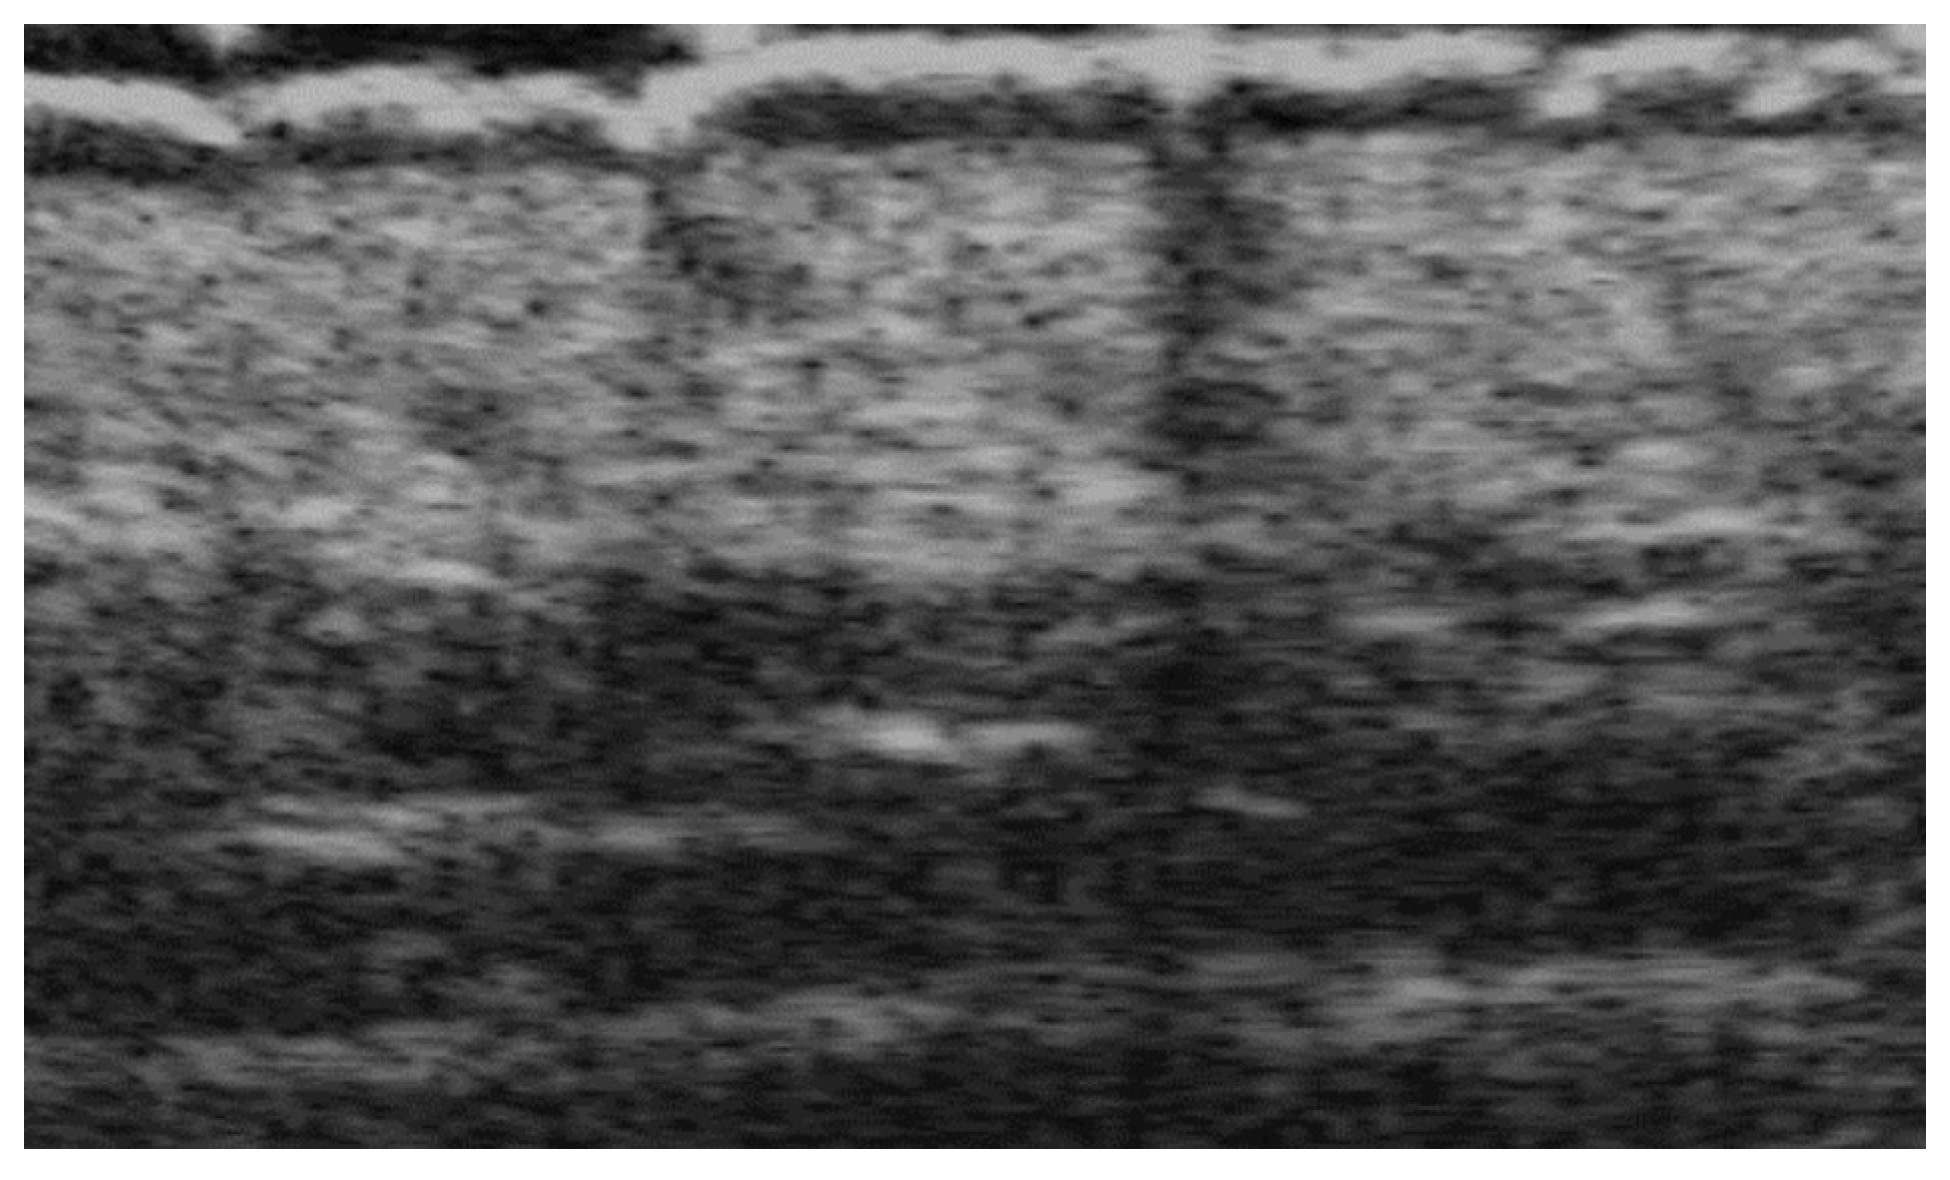

- Ranosz-Janicka, I.; Lis-Święty, A.; Skrzypek-Salamon, A.; Brzezińska-Wcisło, L. An extended high-frequency ultrasound protocol for assessing and quantifying of inflammation and fibrosis in localized scleroderma. Ski. Res. Technol. 2019, 25, 359–366. [Google Scholar] [CrossRef] [PubMed]

- Khorasanizadeh, F.; Kalantari, Y.; Etesami, I. Role of imaging in morphea assessment: A review of the literature. Ski. Res. Technol. 2023, 29, e13410. [Google Scholar] [CrossRef] [PubMed]

- Etesami, I.; Azizi, N.; Sabrinejad, R.; Montazeri, S.; Kamyab, K.; Nasimi, M.; Mahmoudi, H.; Khorasanizadeh, F.; Wortsman, X. Sonographic skin features and shear wave elastography in distinguishing active from inactive morphea lesions: A case-control study. J Am Acad Dermatol. 2025, 92, 155–157. [Google Scholar] [CrossRef] [PubMed]